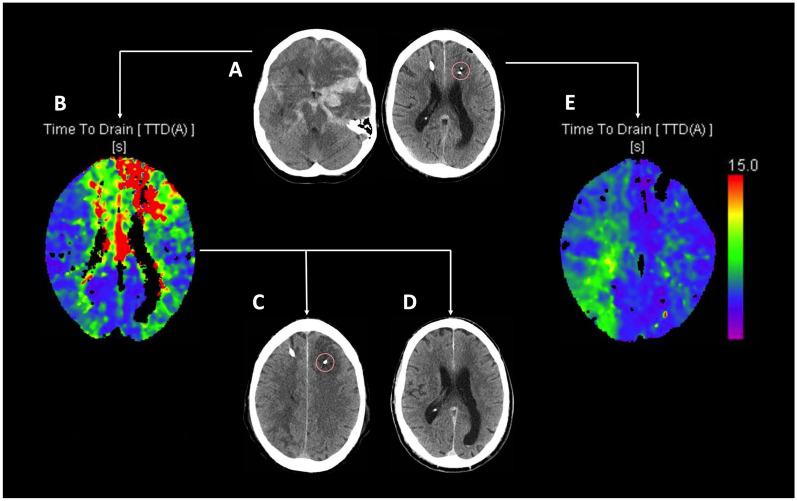

In a cohort of 268 consecutive SAH patients, neuromonitoring-comprising intracranial pressure (ICP) and brain tissue oxygen (PtiO) measurements, and/or cerebral microdialysis-was implemented in 126 (47%) neurologically unassessable patients. Aberrant neuromonitoring measurements triggered CTP, and in cases of confirmed perfusion deficits, first-tier treatment involved induced hypertension. Non-responsive perfusion deficits were further evaluated with conventional angiography, and spasmolysis or angioplasty was performed if suitable vasospasm was identified. DCI-related infarction was noted on CT imaging at discharge, and clinical outcomes were assessed using the modified rankin scale (mRS) at 12 months. Using a generalized linear mixed-effects model (GLMM), factors associated with the occurrence of DCI-related infarction were assessed.

CTP deficits were identified in 72 (57%) patients, of whom 63 (88%) had neuromonitoring probes near the affected areas. In 24 patients (38%), perfusion deficits progressed to infarction, while in 39 (62%), deficits were successfully reversed through induced hypertension or spasmolysis. In a GLMM, lower pressure reactivity index (PRx-OR 2.70, 95% CI 1.04-4.67; p < 0.001) and lower lactate-to-pyruvate ratio (LPR-OR 1.02, 95% CI 1.01-1.03; p < 0.001) were independently associated with better treatment response and reduced infarction risk, after adjusting for clinical hemorrhage severity. These effects were observed more than 24 h before cerebral hypoperfusion. Pooled PRx and LPR over this time frame were not associated with functional outcome.